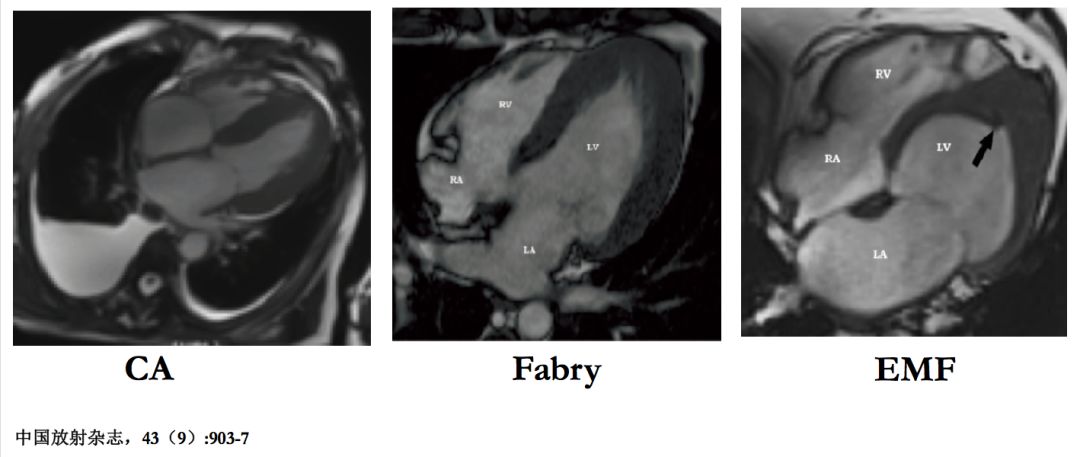

不同的LGE表现可鉴别RCM的类型